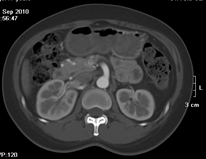

如上圖所示,相鄰的三張軸位圖像未見明顯異常,根據(jù)傳統(tǒng)軸位圖像很難得到準確的臨床診斷。

同一病人利用容積數(shù)據(jù)進行三維處理后,高品質MPR和三維圖像上則清晰顯示了縱向排列的腹腔干與腸系膜上動脈相鄰近,血管發(fā)生變 異,近端血管閉塞,為臨床提供了精確的診斷信息。

從上面的例子可以看到,能否為臨床提供高品質的三維影像成為了16層CT的核心價值,而東芝新一代的 全景三維16層CT擁有最為  先進的3項核心技術,在16層核心價值上的表現(xiàn)自然值得期待。